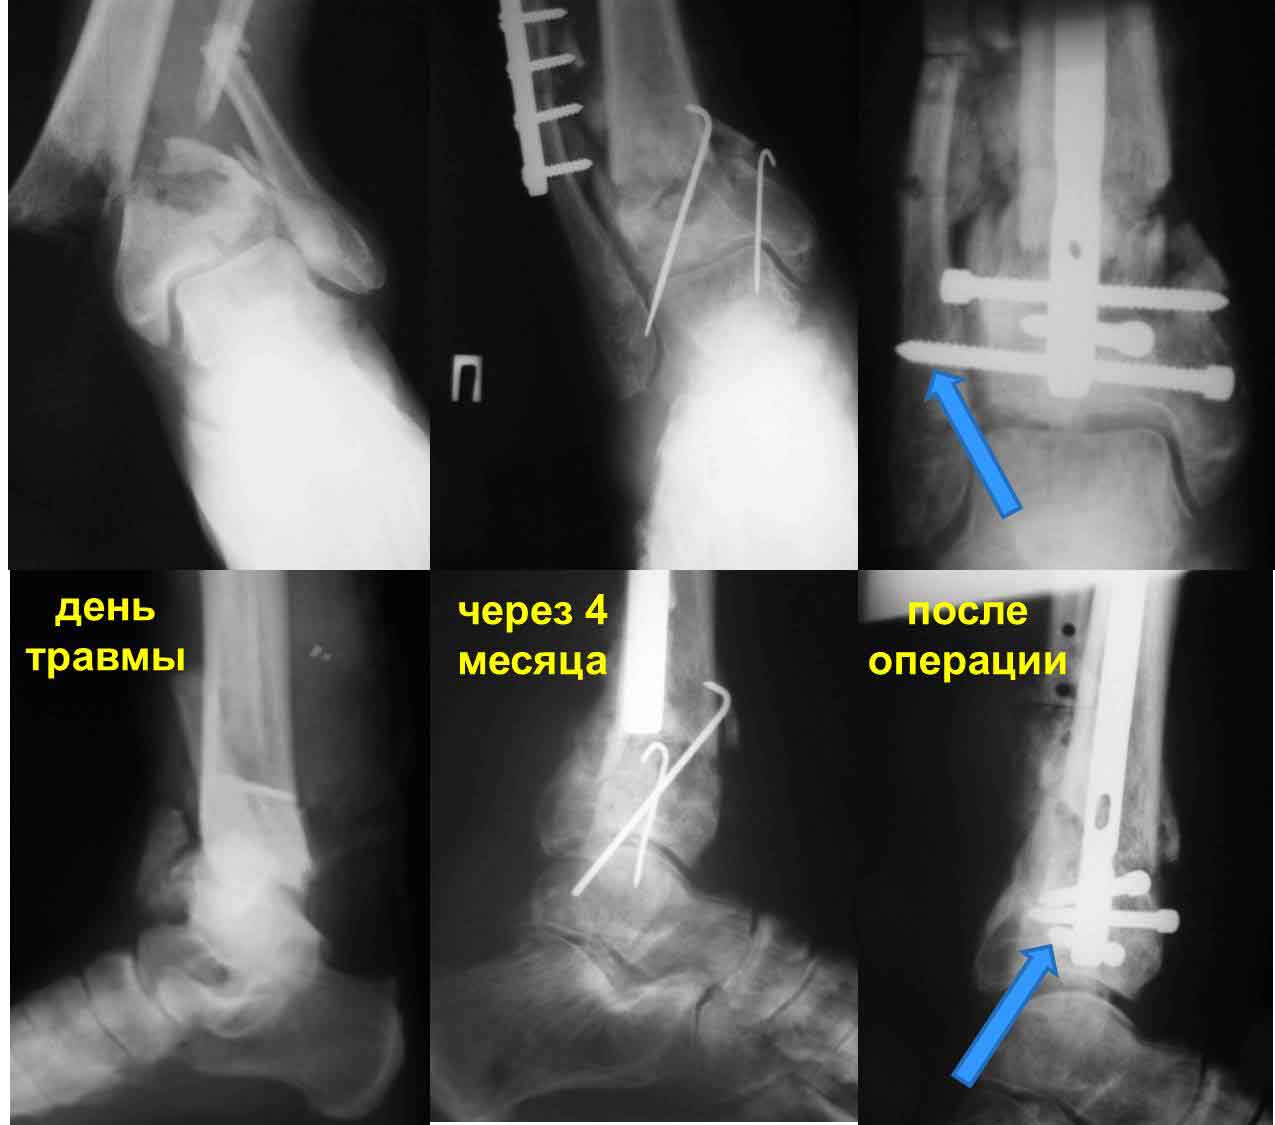

Частота ложных суставов и повторных смещений костных отломков после оперативной стабилизации переломов пилона доходит до 30%. Каждый, кто занимается лечением таких повреждений, наверняка сталкивался с такими осложнениями. Однако лечить такие осложнения в моральном, да и в оперативном плане проще, чем свежие переломы пилона (особенно Ruedi III), поскольку к этому времени становится более или менее понятной судьба голеностопного сустава. Если в достаточной мере владеете блокированным остеосинтезом, то самым оптимальным вариантом, с моей точки зрения, будет следующий. С переднемедиального и латерального доступов выполнить поперечную остеотомию большеберцовой и малоберцовой костей в плоскости параллельной плоскости голеностопного сустава на расстоянии около 3 см от самого сустава. Это минимальное расстояние, которое позволит расположить три блокирующих винта стержня. Важен выбор самого стержня. В данном случае больше всего подходит стержень ChM, имеющий на дистальном конце помимо отверстий в сагиттальной и фронтальной плоскостях и отверстия под углом в 45 градусов, причём на минимальном расстоянии друг от друга. Остетомию и последующую репозицию костных отломков мы выполняем в репозиционном спицевом аппарате. Стержень антеградный. В данном случае не вижу никаких оснований в применении ретроградного стержня, проходящего через здоровый подтаранный и через голеностопный сустав с его до конца неопределённой функцией. Образовавшийся дефект по переднемедиальной поверхности должен быть заполнен костным трансплантатом. Пример похожего случая из нашей практики - в приложенном файле.

Уважаемый VlaD! А что значит синяя стрелка на Вашей презентации? Проведение одного блокирующего винта через обе кости это принципиальный момент операции?

Слайд взят из собственной презентации по лечению переломов пилона. При переломах пилона в большинстве случаев больше всего подвергается разрушению переднелатеральная и латеральная часть большеберцовой кости из-за вальгусной установки пяточной кости и флексии стопы во время травмы. Поэтому самый дистальный винт, который располагается во фронтальной плоскости, мы, путём ротации стержня, стараемся провести и в малоберцовую кость, чтобы конец блокирующего винта располагался в прочной кости и выполнял свою функцию. Не знаю, насколько это принципиально, но так как обе кости связаны между собой синдесмозом, наверное, в этом есть рациональное зерно.